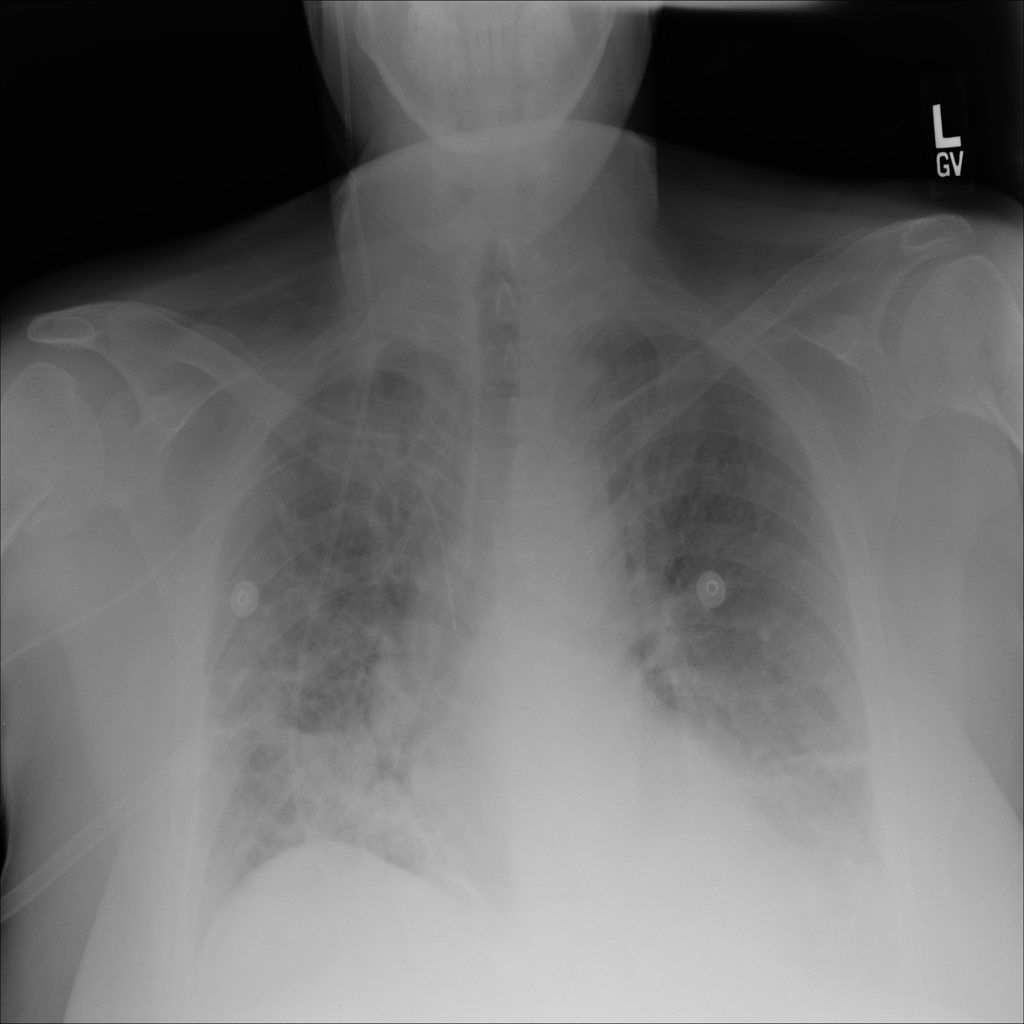

PAT-EBE1 · IMG-019Pneumonia

PAT-EBE1 · IMG-019

AP